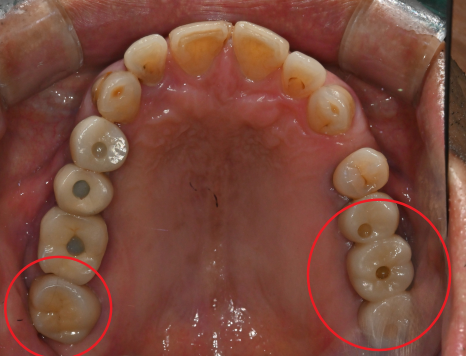

치료 전

치료 후

· 20대 여성 환자

치과 공포증으로 치료를 미루다 충치 진행

→ 수면으로 양측 어금니 크라운 치료 및

매복 사랑니 발치 동시 진행